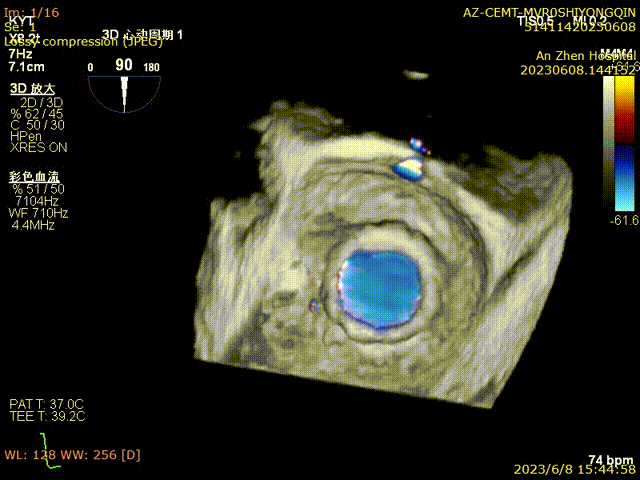

术前食管超声检查确认人工二尖瓣衰败,重度关闭不全

术后超声评估无反流